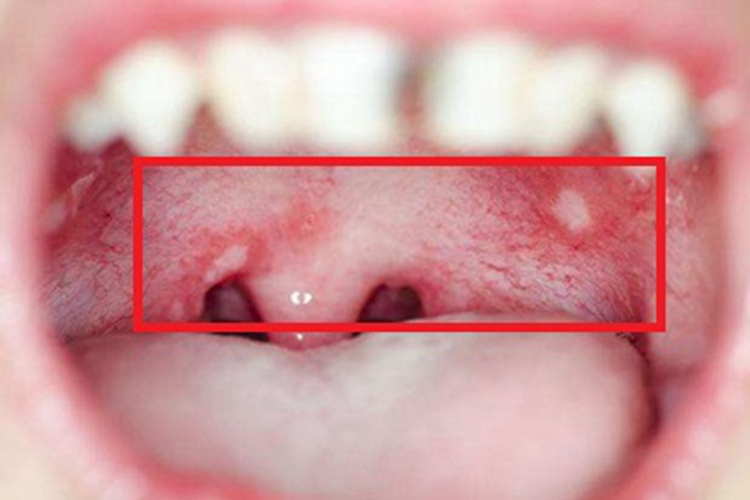

疱疹性口炎:起病时发热可达38-40℃,1-2日后,口腔黏膜出现单个或成簇的小疱疹,直径约2mm,周围有红晕,迅速溃破后形成溃疡,有黄白色纤维性分泌物覆盖,如同白点,多个溃疡可融合成不规则的大溃疡。由于疼痛剧烈,患儿可表现拒食、流涎、烦躁,常因拒食啼哭才被发现。